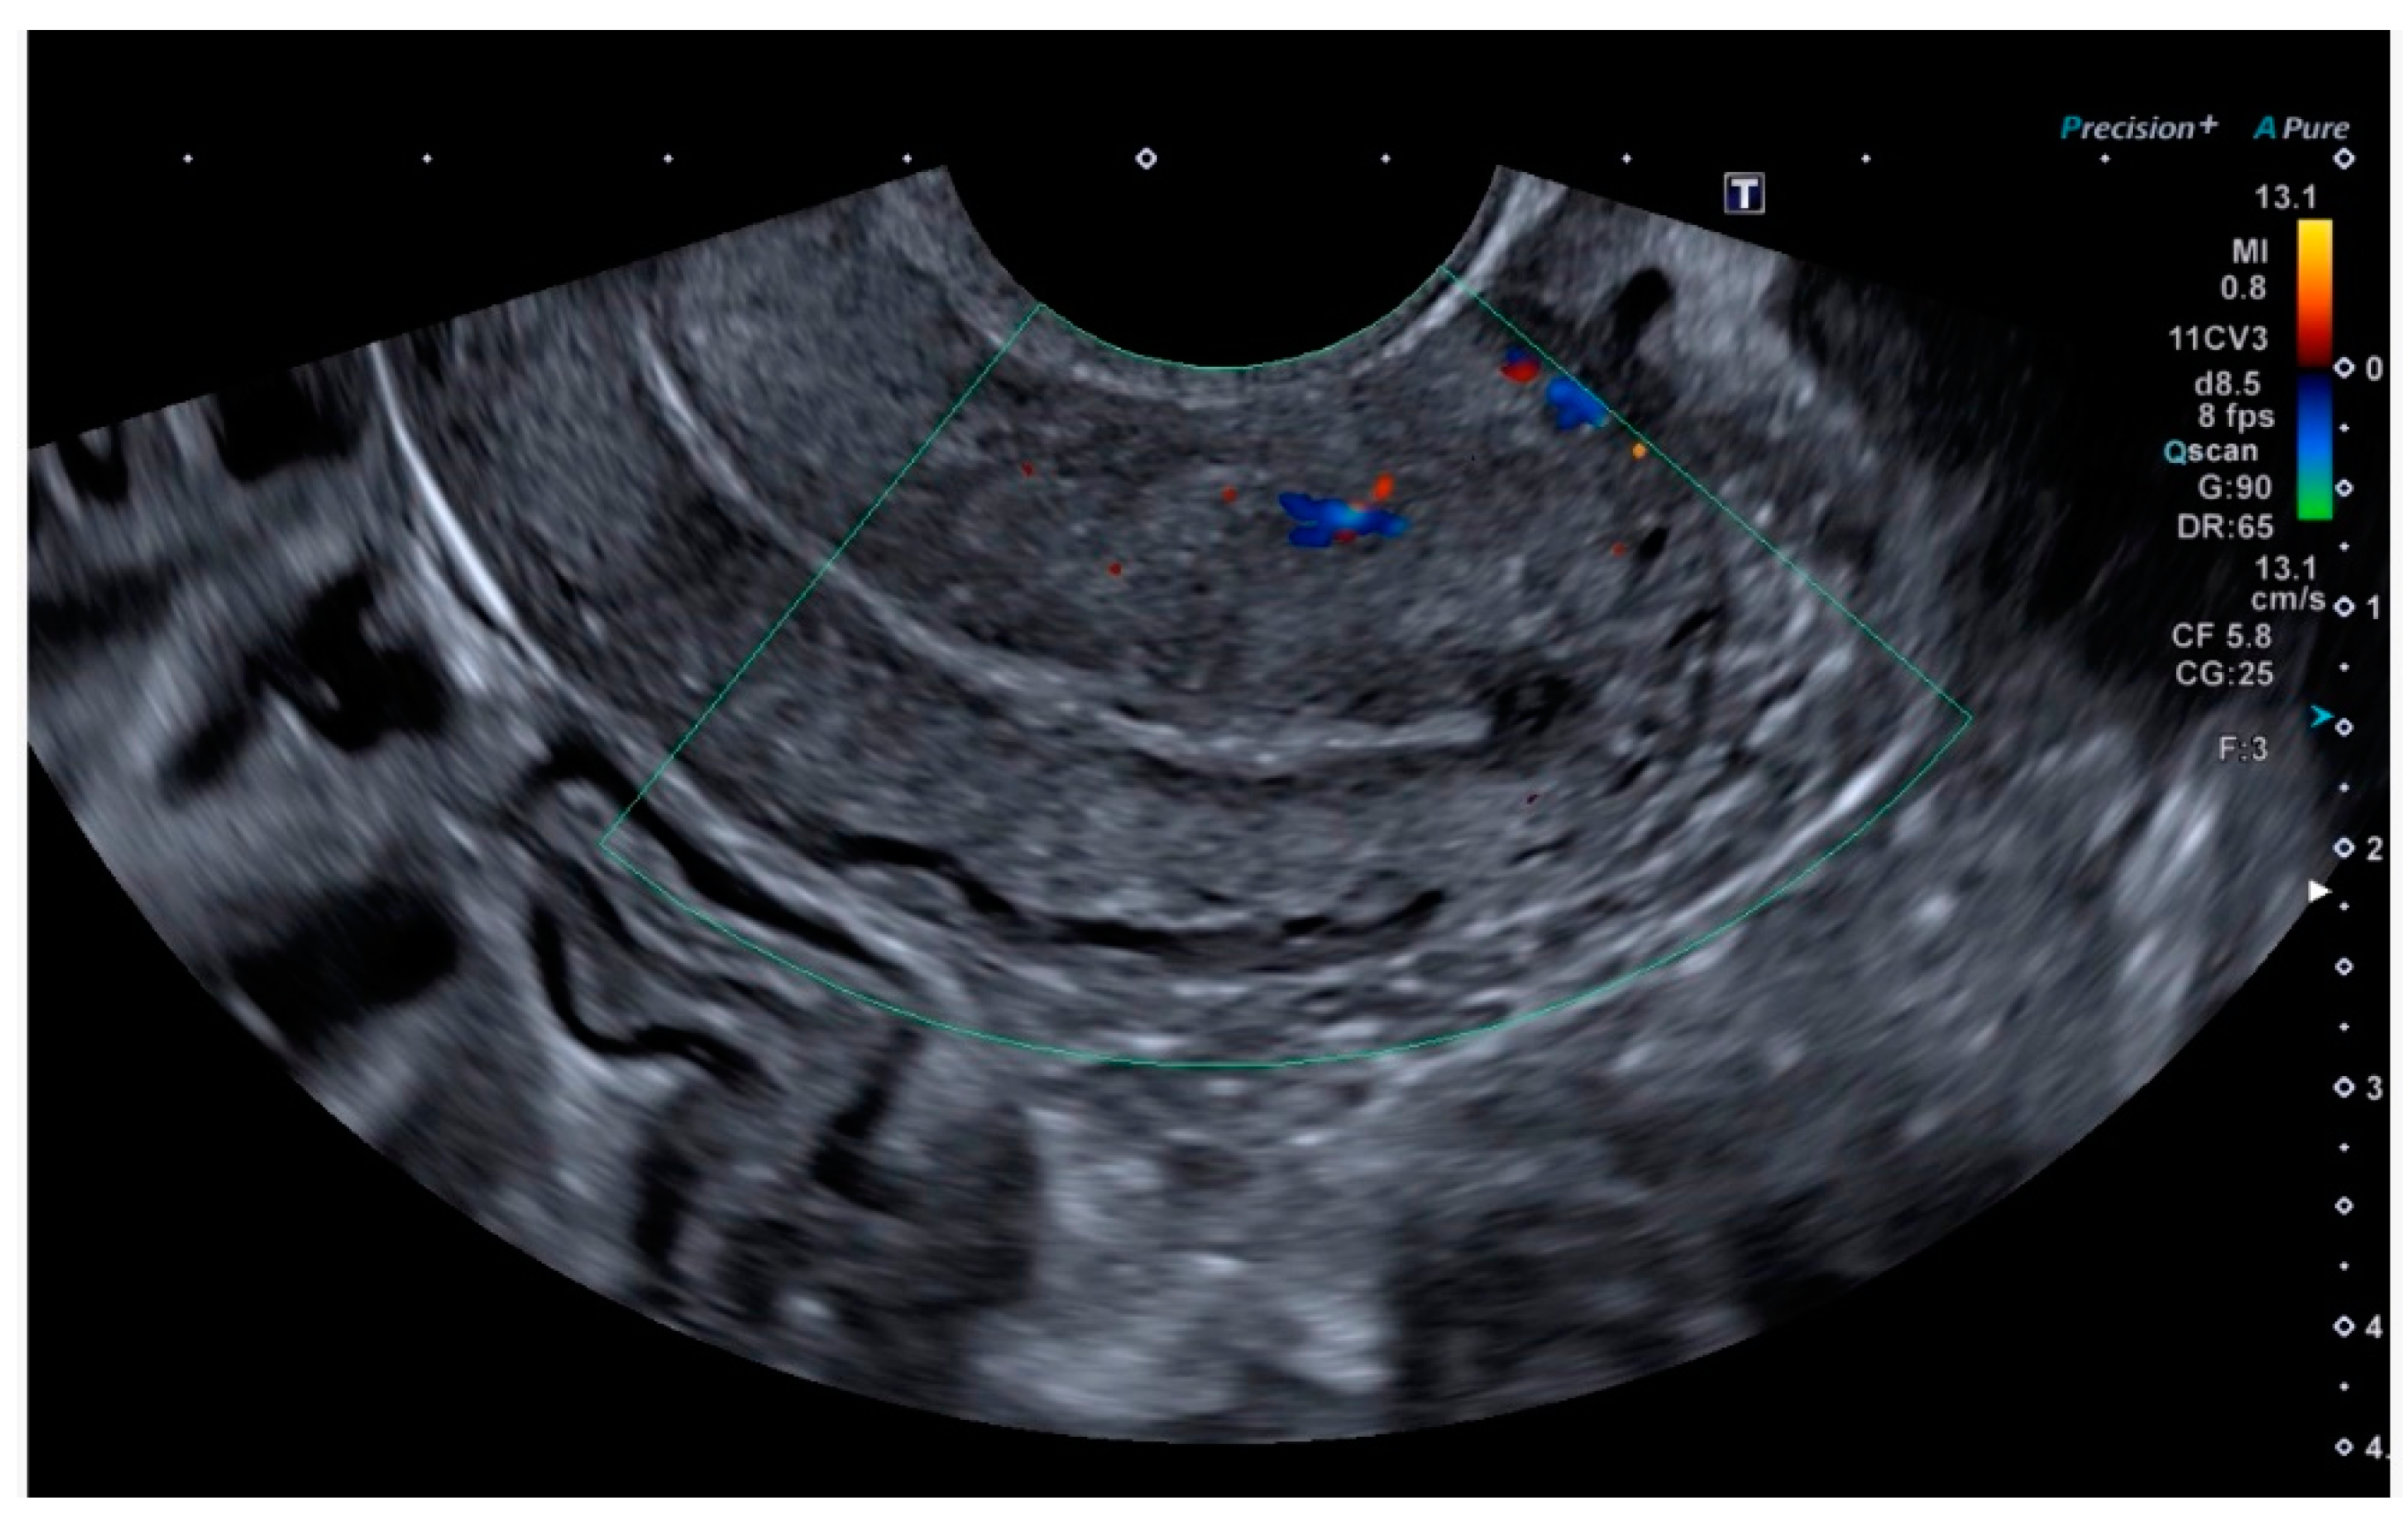

Finally, the vascular surgeons ruled out selective arterial embolisation because the size of the lesion made complete and effective embolisation impossible. Conservative treatment with combined hormonal contraceptives was chosen because the patient’s reproductive desires were not fulfilled. After four months of being asymptomatic and under treatment with combined hormonal contraceptives, the patient presented for follow-up, at which time no AVM was observed on the ultrasound, either in B-mode or colour Doppler (Figure 5 and Figure 6).

Figure 6. Absence of colour Doppler uptake.